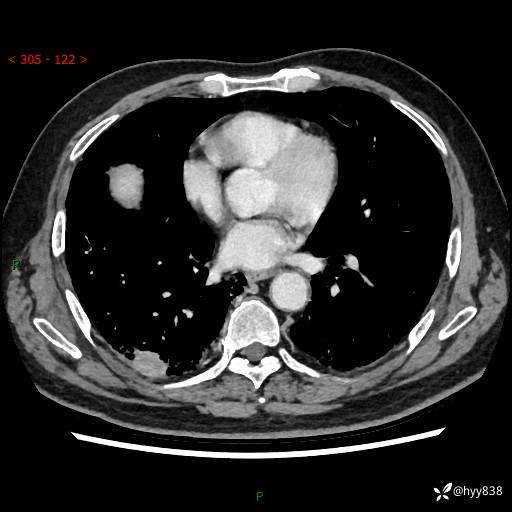

71岁/男,咳嗽伴气促半月。一年前肺手术史,又见两个结节,穿刺结果意外---结果公布~

【现病史】:患者半月前无明显诱因出现咳嗽、咳痰,为白色粘痰,无明显加重与缓解因素,伴气促,无发热,无大量脓痰,无胸痛、咯血,无哮鸣音,到我院就诊,胸部CT示右肺结节增大,并口服药物治疗无明显好转,具体用药不详,为求进一步治疗随来我院,经门诊以“孤立性肺结节”收入我科。 病程中患者精神、饮食可,睡眠不佳,大小便正常,体力下降,体重未见明显下降。

[既往史]:2022-06于当地第一人民医院确诊慢阻肺,现规律使用杰润(1次/日);2023-04-06于当地市第一人民医院行胸腔镜右肺上叶楔形切除术+右肺上叶切除术+淋巴结清扫术+胸膜黏连松解术,确诊为右肺鳞癌 pT2aN0M0 Ib期

【检查】:胸部CT平扫+增强